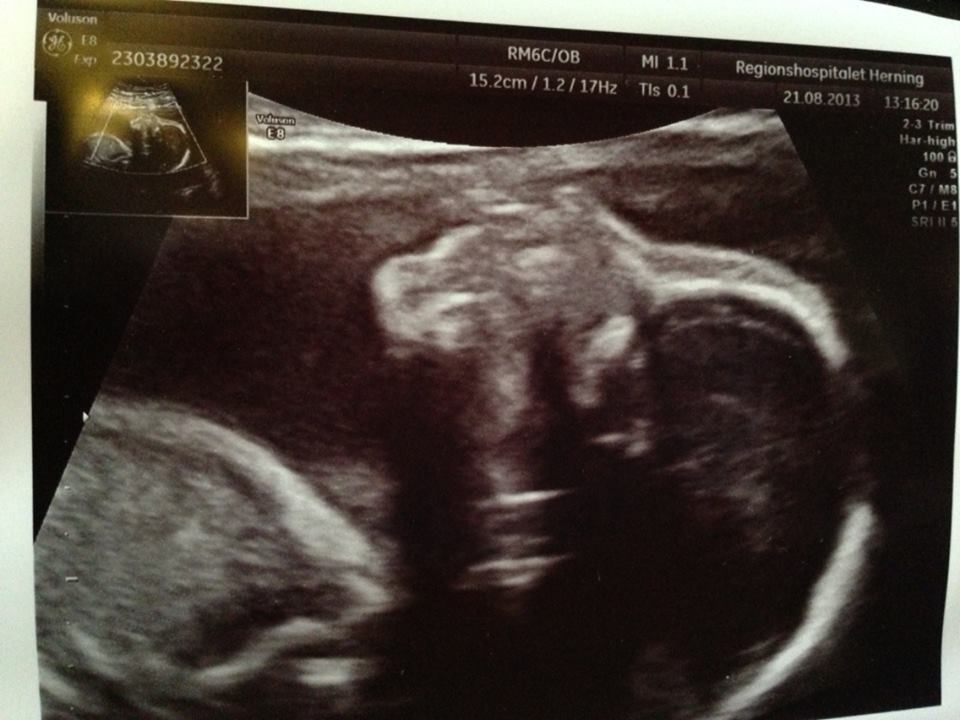

og tvillingerne havde det som en drøm vi fik dog konkluderet bette pigen ikke er fotogen, og at jeg venter en håndbold spilelr og fodbold spiller der overhovedet ikke kan ligge stille

vi fik lavet vækstscanning som også var super fin nu  men prinsessen vejerihvertfald 571 og er 28 cm, og prinsen vejer 584 og er 30 cm så de ligger tæt.

og self skal i da også lige have lov at se billeder af de skønne unger

billede 1 er af prinsessen og billede 2 af prinsen

Hvor er det nogle fine billeder

Ps. Dit CPR nummer er tydeligt på billederne